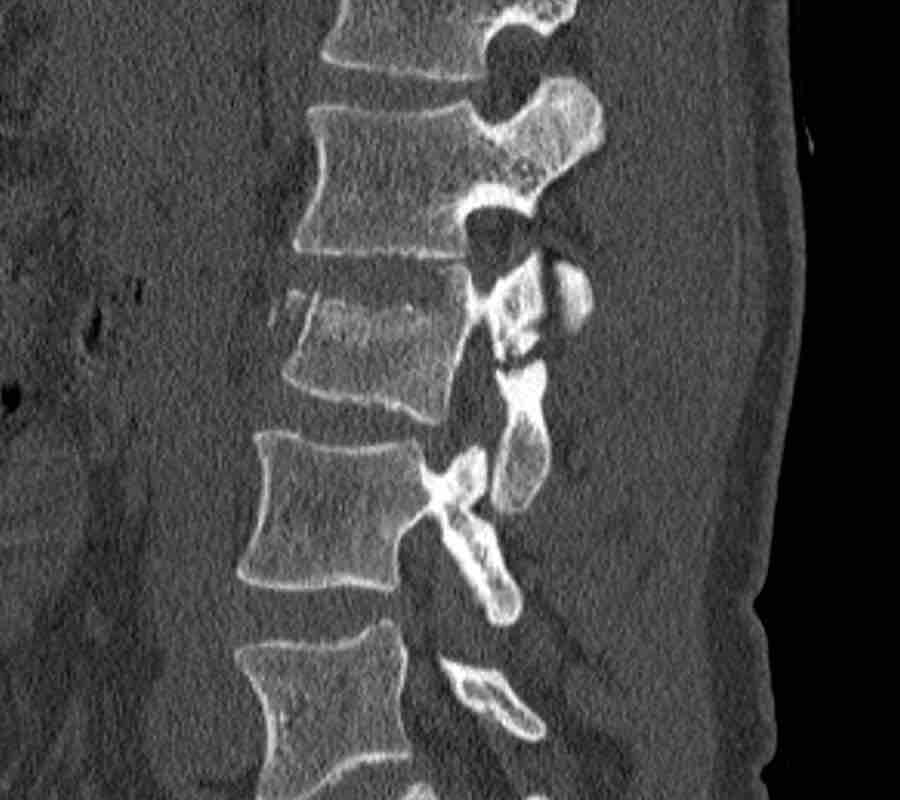

Scroll through images.

What is the highest AO-level?

Findings

- No dislocation ( no C type).

- Mainly horizontal fractures of spinous processus at multiple levels (B-type).

- Split fracture L2 (type A2).

Conclusion

Injury type B2 + A2 at level L2.

The combination of these fractures make it difficult to comprehend what exactly has happened.

The AO spine classification is only designed to classify these injuries as simple as possible.